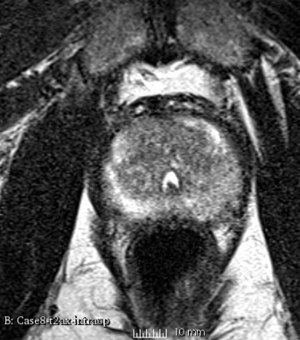

We used this sample data with Reader 1 segmentations to visually evaluate differences in the registration results. All three results of BRAINSFit with ITKv3 in Slicer 3.6 look reasonable. Using BRAINSFit with ITKv4 in Slicer 4.4 creates a reasonable result for Case 7, but look strongly distorted towards the edges of the bounding box in Case 8 and 9.

Case 9

Reference intraop volume

Reg Result Slicer 3.6 with ITKv3

Reg Result Slicer 4.4 with ITKv4